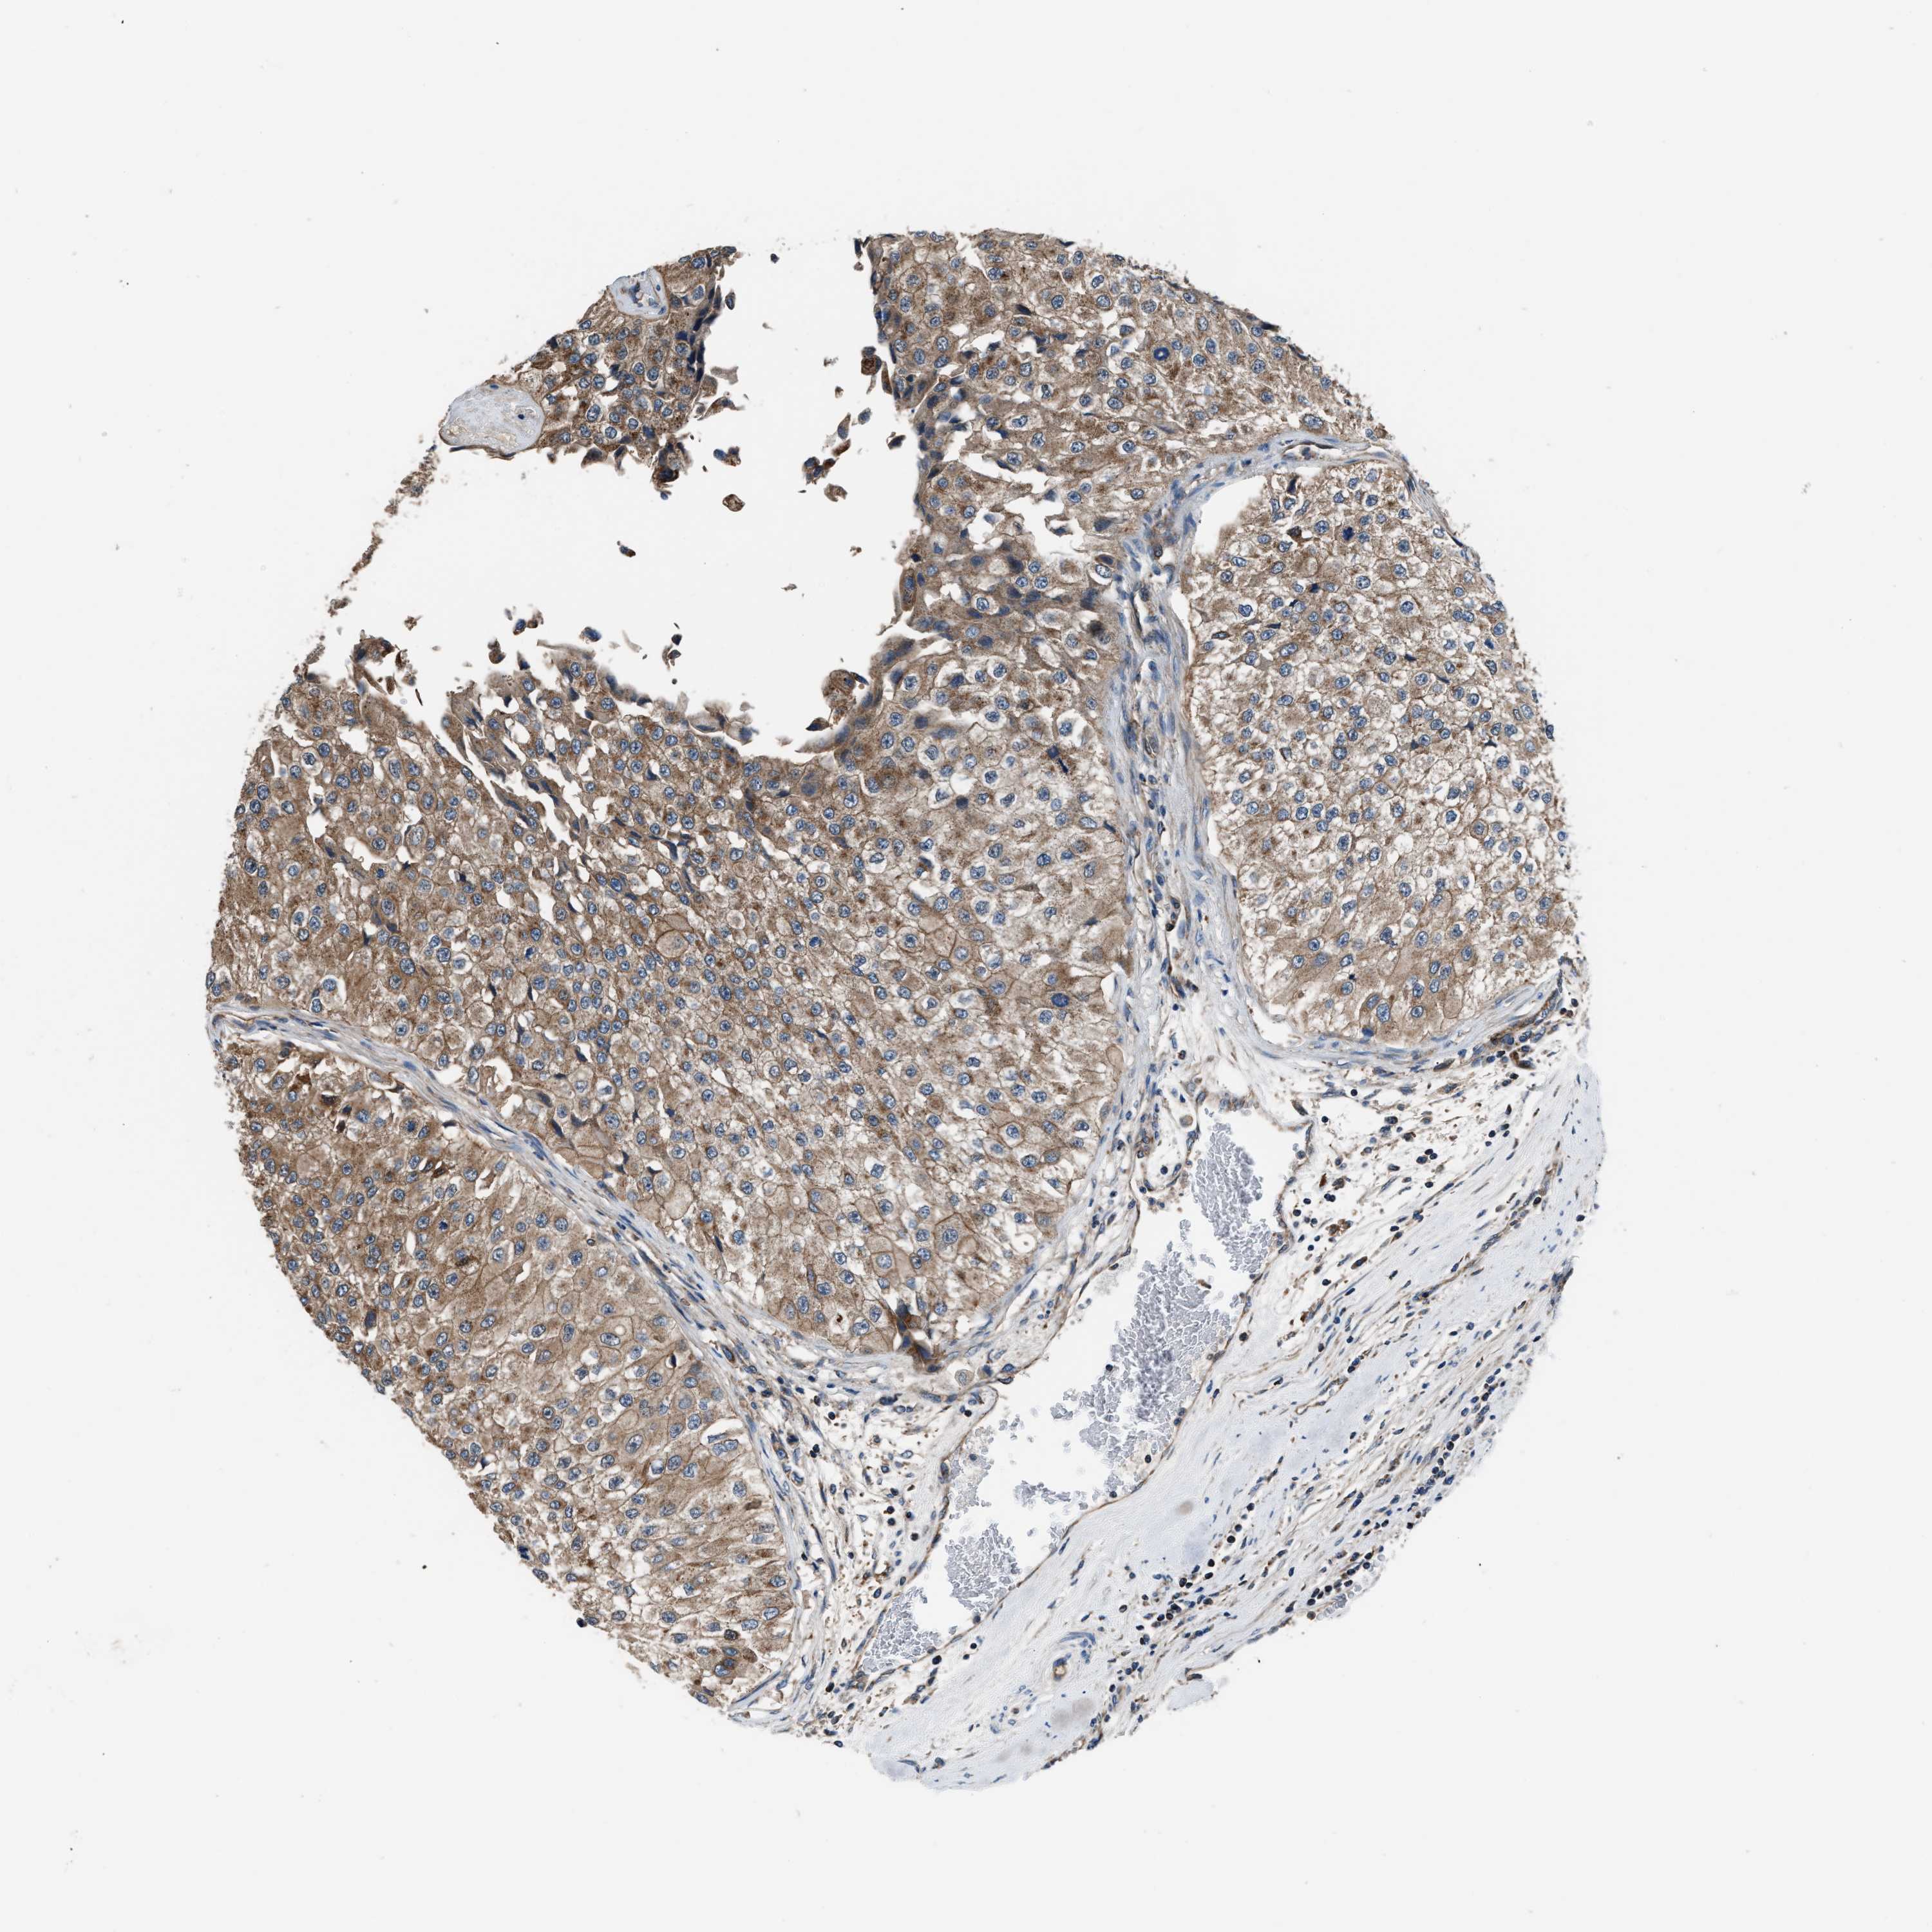

UROTHELIAL CANCER - Protein expressioni

A mouse-over function shows sample information and annotation data. Click on an image to view it in a full screen mode. Samples can be filtered based on level of antibody staining by selecting one or several of the following categories: high, medium, low and not detected. The assay and annotation is described here.

Note that samples used for immunohistochemistry by the Human Protein Atlas do not correspond to samples in the TCGA dataset.

Antibody stainingi

Antibody staining in the annotated cell types in the current human tissue is reported as not detected, low, medium, or high, based on conventional immunohistochemistry profiling in selected tissues. This score is based on the combination of the staining intensity and fraction of stained cells.

Each image is clickable and will lead to virtual microscopy that enables deeper exploration of all samples and also displays staining intensity scores, fraction scores and subcellular localization as well as patient and tissue information for each sample.

Antibody HPA020735

Staining

High

Medium

Low

Not detected

Intensity

Strong

Moderate

Weak

Negative

Quantity

>75%

75%-25%

<25%

None

Location

Urothelial carcinoma, Low grade

Urothelial carcinoma, High grade